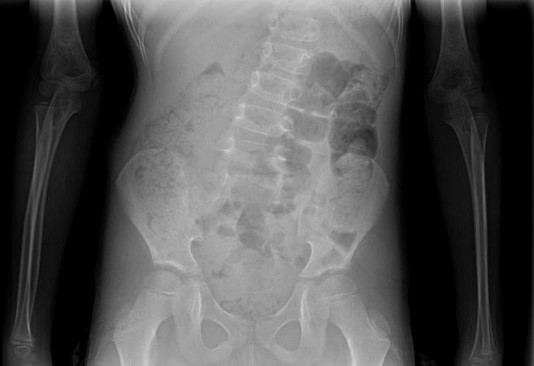

男 15岁

脊柱侧弯畸形

AEC 80KV

脊柱侧弯畸矫形术前检查

通过全景拼接图像可以清晰显示脊柱侧弯的具体细节,为矫形手术提供更详尽的资料。